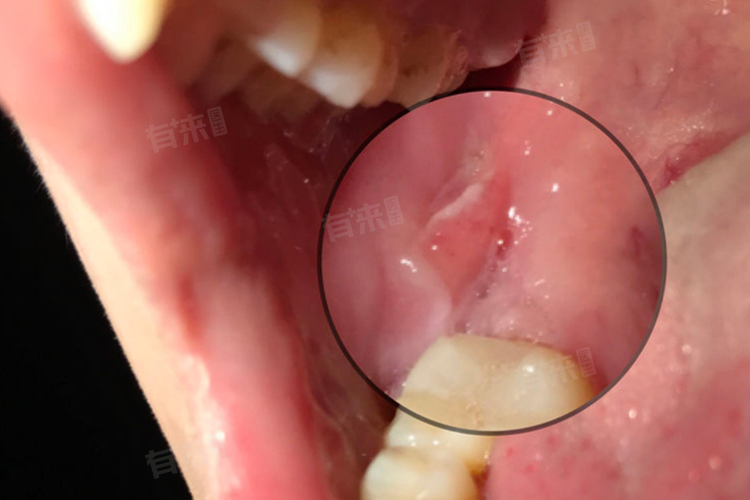

2、固定义齿修复:固定义齿需以缺牙间隙两侧健康牙齿为基牙,通过磨除部分牙体组织制作烤瓷冠或全瓷冠,将义齿固定于基牙上,形成“牙桥”。其优点是修复周期较短(2-3周),咀嚼功能恢复较好,无需每日摘戴。但该方法不可逆地损伤邻牙,基牙承担额外咬合力,可能导致基牙牙髓损伤或牙周组织负担加重。适用于缺牙数量少(1-2颗)、邻牙稳固且牙体组织健康的患者。选择全瓷冠可避免金属离子析出,生物相容性更佳,尤其适合对美观要求高的前磨牙缺失者。